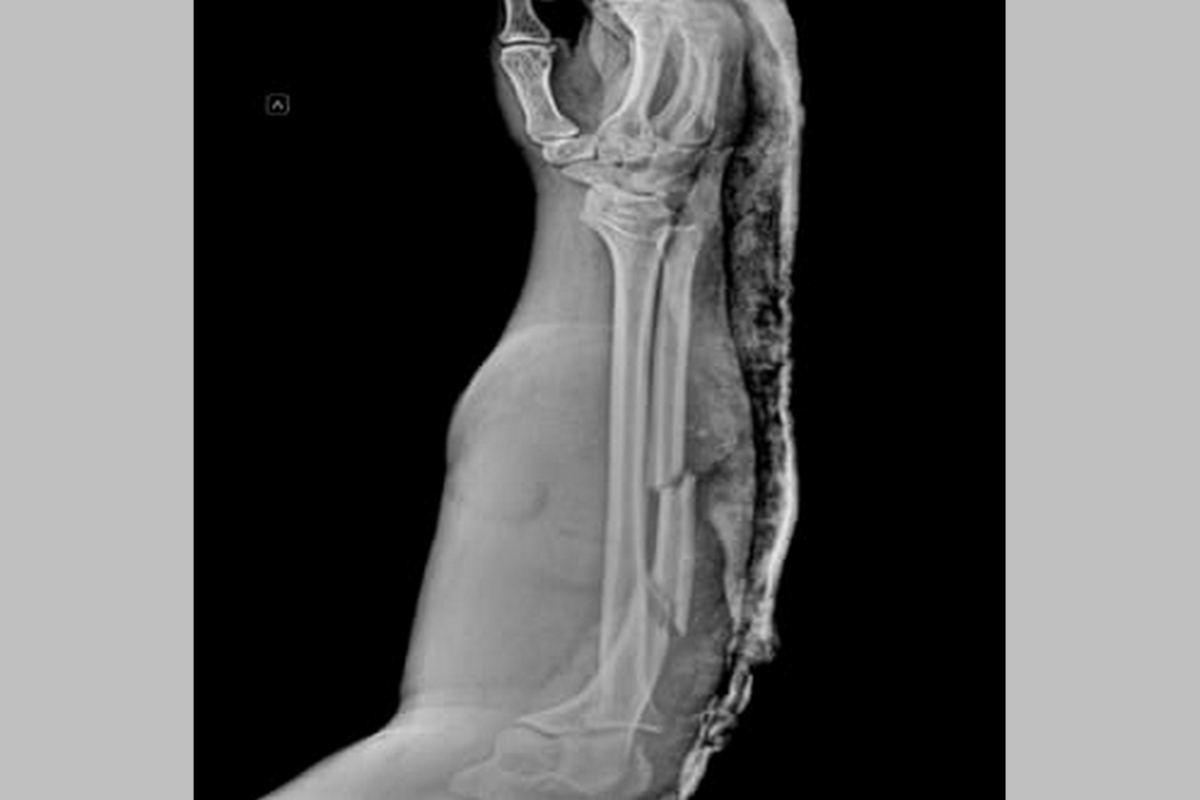

Фото: Министерство здравоохранения Воронежской области

На первом этапе лечения была выполнена хирургическая обработка раневой поверхности с применением пластики местными тканями. Для стабилизации перелома локтевой кости предплечья был использован аппарат внешней фиксации (КСВП), обеспечивающий быструю фиксацию отломков трубчатых костей.

На заключительном этапе, через три недели, выполнена открытая репозиция (сопоставление костных фрагментов после перелома) и погружной остеосинтез локтевой кости с использованием пластины и винтов для фиксации костей.